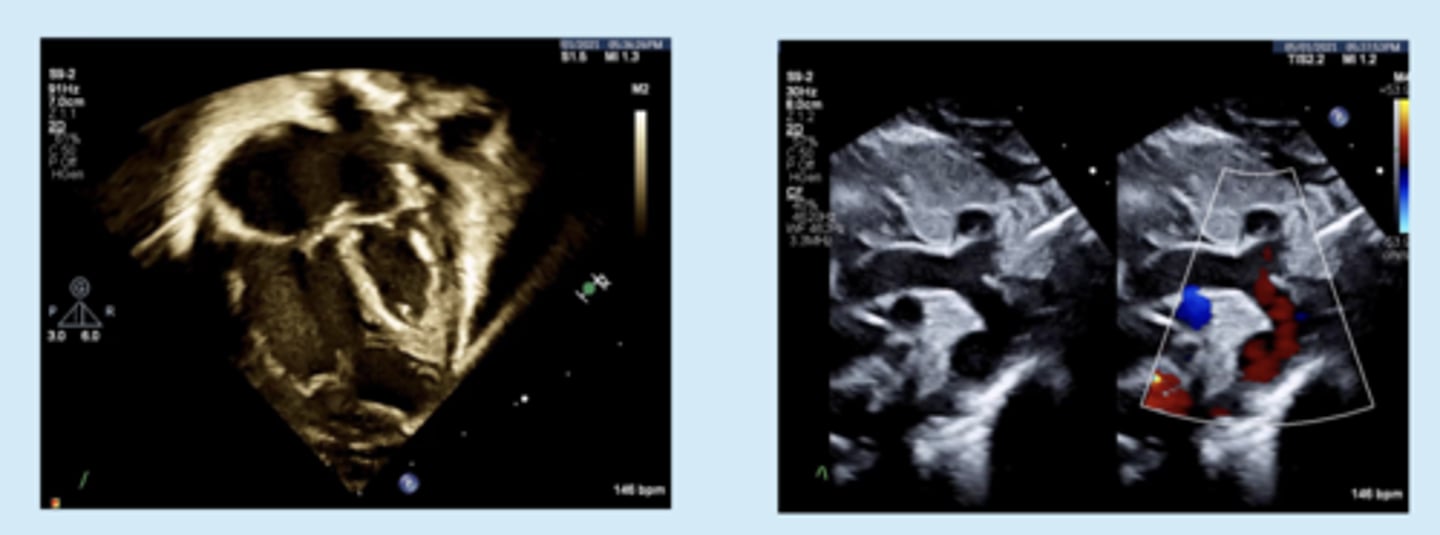

COA Coarctation

WHAT LESION?

COA